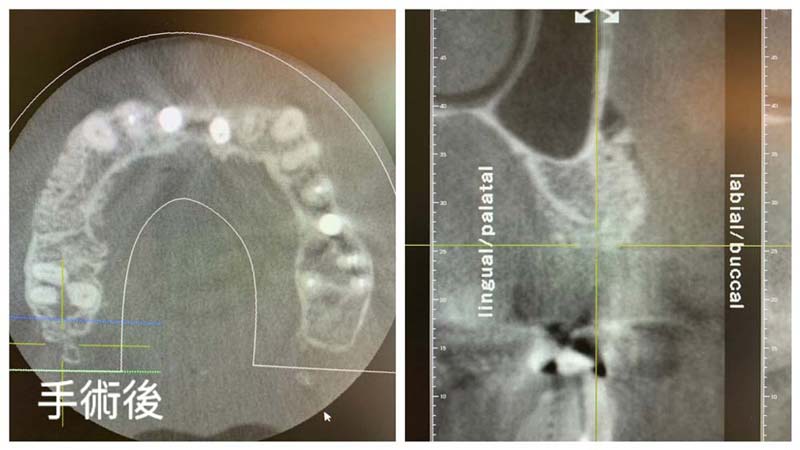

以人工骨粉及人工再生膜施作之齒槽骨再生術,能有效回復齒槽骨厚度,以保障後續植牙治療能建立在高品質的地基上